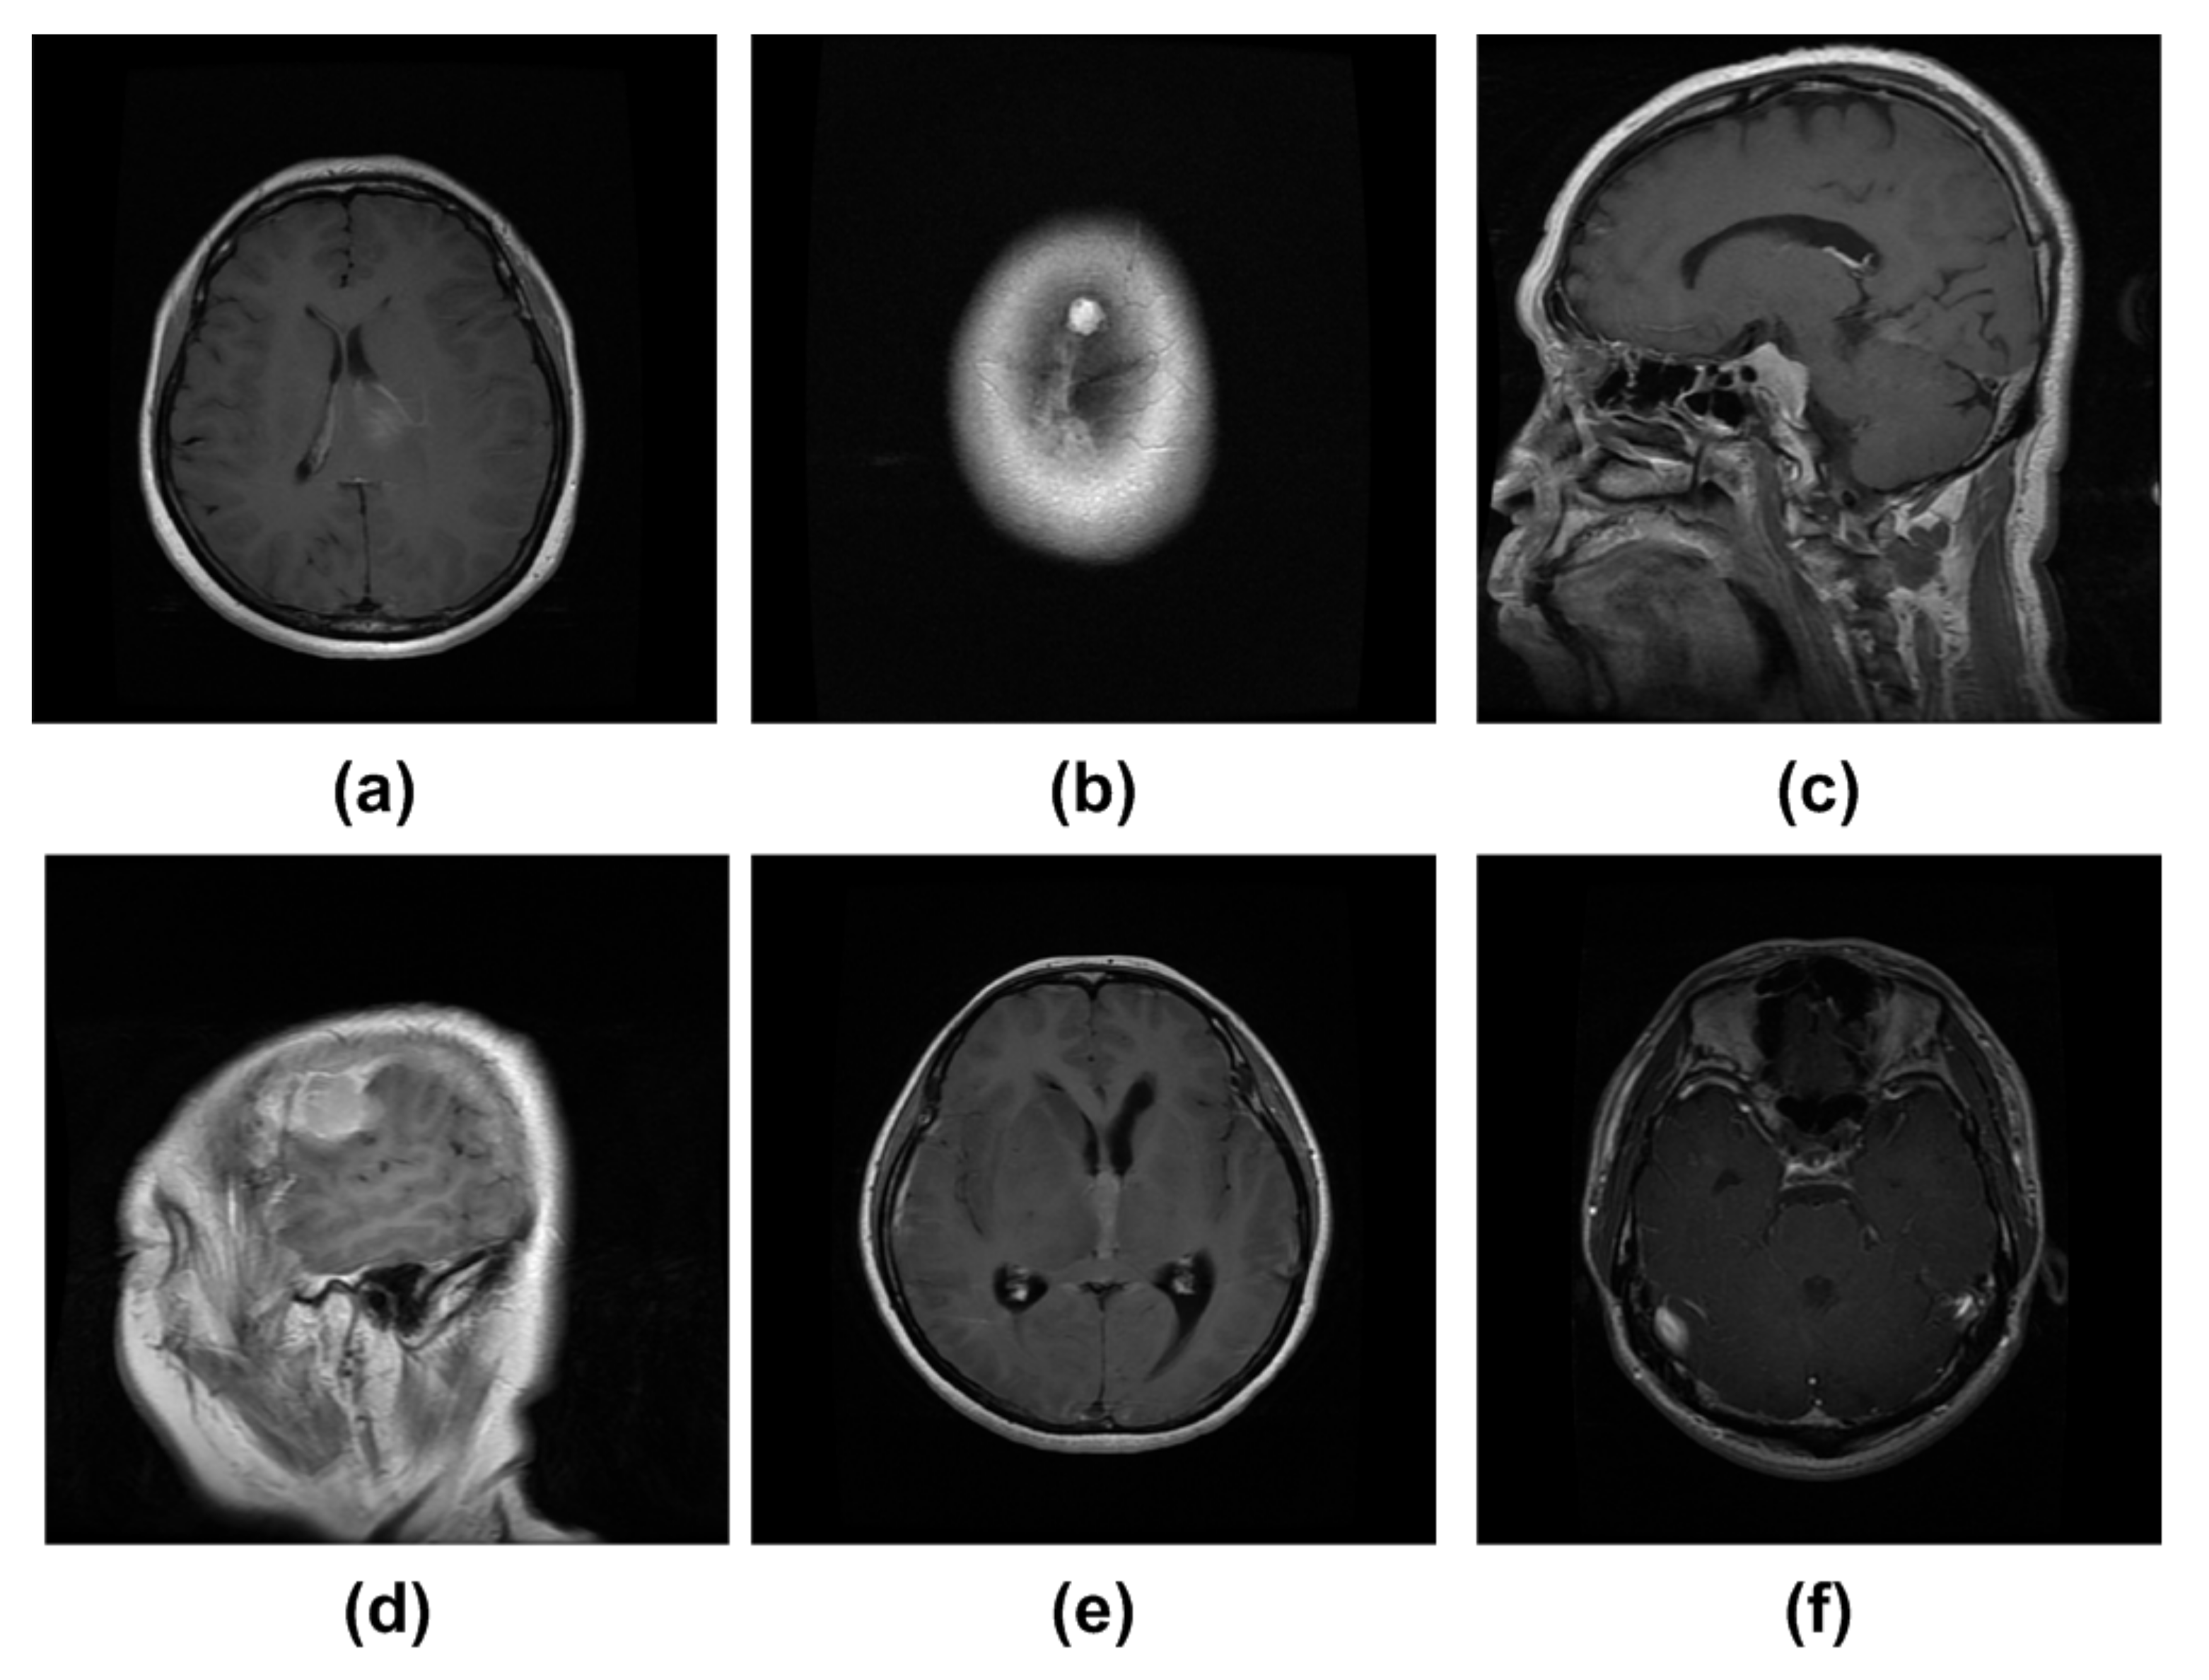

4.1. Dataset